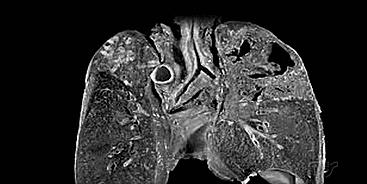

图片来源:丁香医生

图片来源:腾讯医典